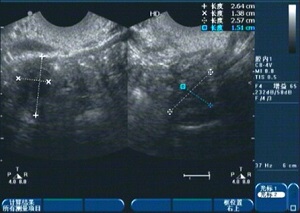

1、診斷:醫生會(huì )通過(guò)詢(xún)問(wèn)病史、體檢及輔助檢查(如超聲檢查、激素檢測等)來(lái)確定診斷。